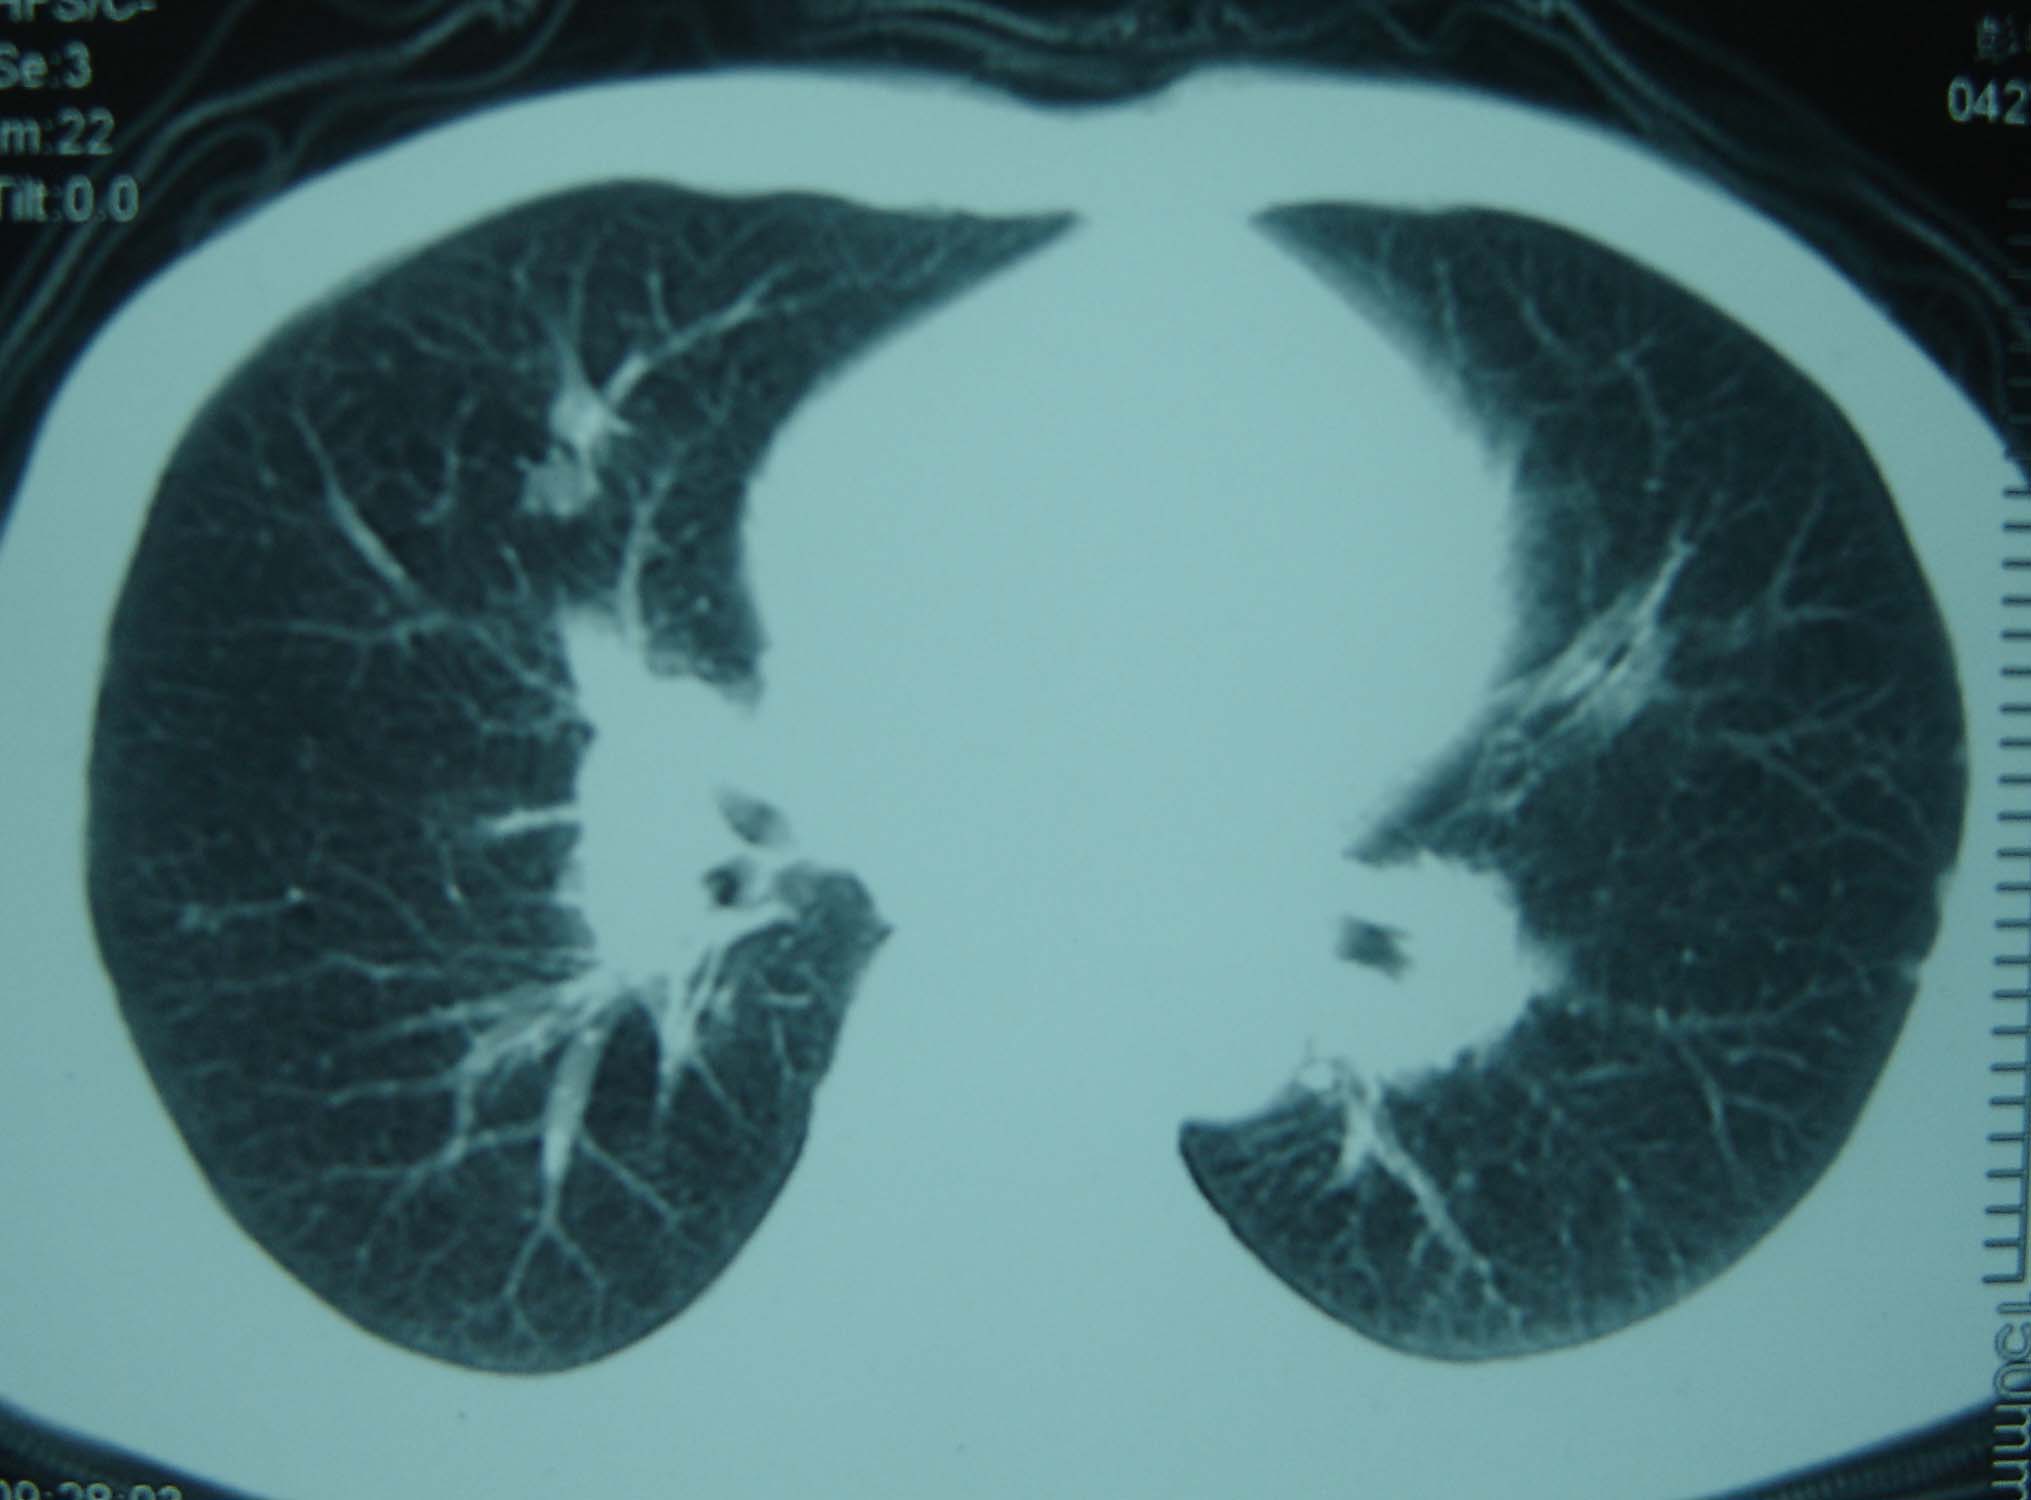

标题: CT25321:两肺多发结节 请会诊 [打印本页]

标题: CT25321:两肺多发结节 请会诊

男 、43岁,咳嗽胸痛,装修工,平时接触粉尘较多,有吸烟史10多年,纤维支气管镜检查未发现异常,胃镜、腹部b超检查亦未发现异常,颈部淋巴结活检未发现肿瘤细胞。

不能排除转移,如果不能找到原发灶,只有短期随访。

结节病?转移瘤?

结节病。

转移瘤?

1)考虑双肺及胸膜多发性转移瘤。2)肺气肿。

双肺结节病。